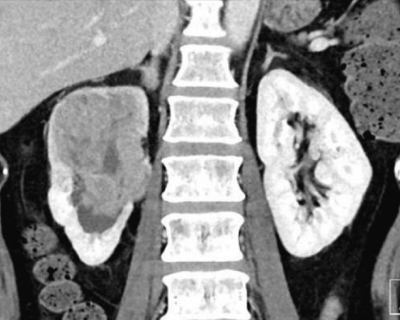

尿所見:蛋白1+、糖(-)、潜血3+、沈渣に赤血球多数/1 視野、白血球2〜5/1 視野。尿細胞診はクラスⅤ。血液所見と血液生化学所見とに異常を認めない。胸部エックス線写真で異常を認めない。腹部造影 CT の水平断像と冠状断像とを別に示す。全身検索でリンパ節転移と遠隔転移とを認めない。膀胱鏡検査で異常を認めない。尿管鏡による生検で高異型度尿路上皮癌の細胞を認める。